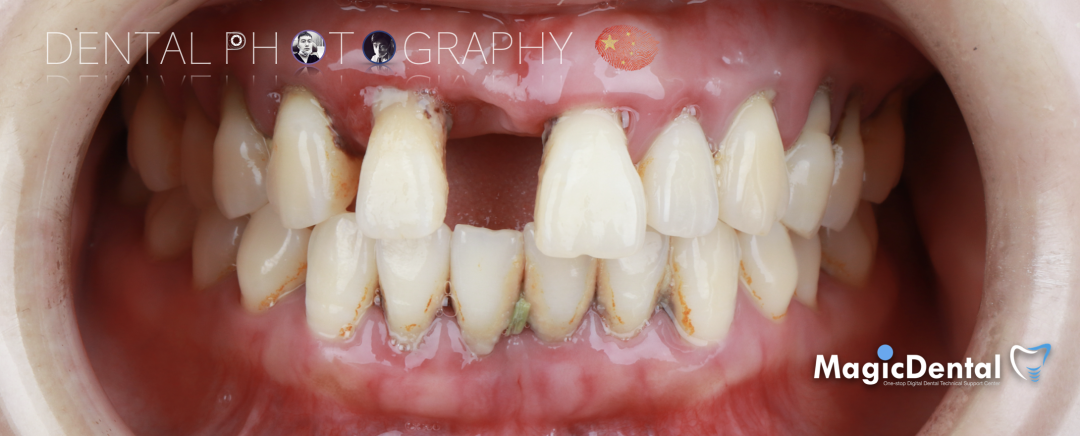

患者术前口内及面相照片

口腔检查:口腔卫生差,全口牙龈红肿,牙颈部大量牙结石附着,伴有不同程度附着丧失,牙周探针深度普遍大于8mm,上颌牙列I~III°松动。

CT显示牙槽骨水平吸收严重,大多数吸收至根尖。

诊断: 全口慢性牙周炎,上颌牙列缺损。

治疗计划:拔除上颌牙列,种植6枚奥齿泰种植体,马龙桥修复。下颌行牙周治疗+纤维带固定。